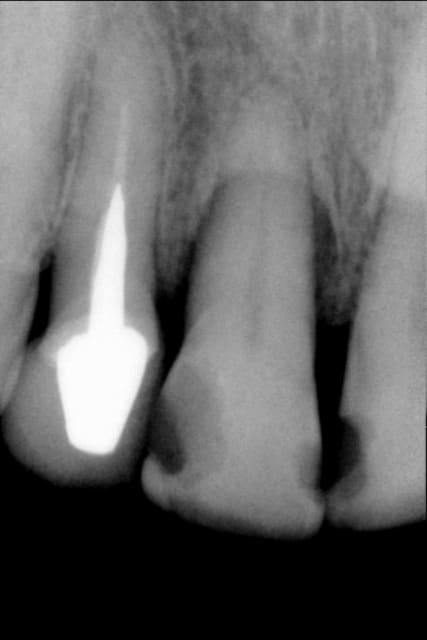

j'ai traité la dent, voir la deuxiéme radio

Un beau canal latéral

jeff2 ton cas pour moi c'est pas un canal lateral au depart c'est une felure car sur la derniére image il me semble qu'il y a un decrochement en mesial qui est apparu et qui traduit le deplacement Non???. D'ailleurs le parodonte environnant n'est pas stabilisé.......enfin me semble-t -il

canal lat ou fracture? la derniere radio ne Jeff2 ne m'a pas encore convaincu...mais c'est vrai que l'endo est tres belle...